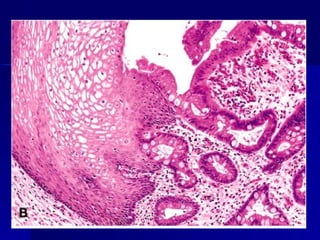

 Ejemplos: metaplasia escamosa, Esófago de Barret.

Ejemplos: metaplasia escamosa, Esófago de Barret.

1. Metaplasias epiteliales:

Metaplasia epitelial escamosa: mucosas, conductos,

bronquios, cervix, endometrio y próstata.

Metaplasia intestinal: En las gastritis y colecistitis

crónicas y esófago de Barrett.

METAPLASIA METAPLASIA  Es unaalteración reversible en la que un tipo Es una alteración reversible en la que un tipo celular maduro es sustituido por otro (epitelial o celular maduro es sustituido por otro (epitelial o mesenquimatoso) mesenquimatoso)  Ejemplos: metaplasia escamosa, Esófago de Barret. Ejemplos: metaplasia escamosa, Esófago de Barret.  Los fibroblastos pueden transformarse en Los fibroblastos pueden transformarse en osteoblastos o condroblastos. osteoblastos o condroblastos.  Existe una reprogramación genética en las células Existe una reprogramación genética en las células mesenquimatosas indiferenciadas de los epitelios mesenquimatosas indiferenciadas de los epitelios por citocinas, factores de crecimiento. por citocinas, factores de crecimiento.

1. Metaplasias epiteliales: Metaplasiaepitelial escamosa: mucosas, conductos, bronquios, cervix, endometrio y próstata. Metaplasia epitelial apocrina: glándulas exocrinas de la mama. Metaplasia intestinal: En las gastritis y colecistitis crónicas y esófago de Barrett. Metaplasia antral: En la vesícula biliar y cuerpo gástrico.